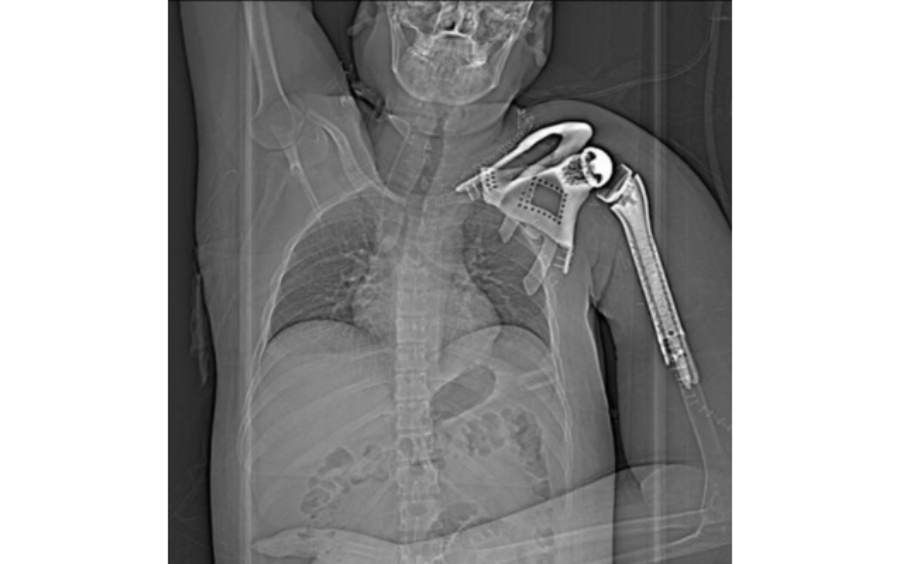

Onco Orthopedic Dr. Pramod Chinder surgeon in Bangalore, decided the surgical plan- Considering the extensive extent and size of lesion, the surgery was divided into two parts performed on two different days: day 1 involved wide resection of the tumor in the left proximal humerus encasing the clavicle and scapula. Along with the tumor mass, upper half of scapula, lateral 2/3rd of clavicle and proximal half of the humerus had to be removed. Day 2- involved shoulder reconstruction with the help of 3D printed humerus, scapula, clavicle, and reverse shoulder arthroplasty implants. Incredible team discussed with Surgeon, the designing and entire manufacturing process. Read more

Implant was manufactured under ISO 13485 guidelines & tested to give an accurate fit & utmost safety.

Once the resection was done, customized implant from 3D Incredible was implanted along with standard size shoulder joint prosthesis. Implant was manufactured using Ti6Al4V-ELI as per anatomical requirement, contour and bone thickness which are patient specific. 3D Incredible customized implant helped to reduce OT time as there was no further adaption of standard implant required on OT Table. Read more